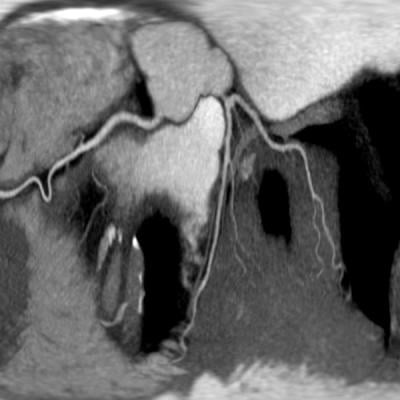

An image of coronaries from Withinsight Framework 3.0

December 4, 2013 — Claron Technology, Inc. debuts version 3.0 of Withinsight Framework (WIF), an advanced platform that accelerates development of medical image visualization applications, at the 2013 Radiological Society of North America (RSNA) conference. This next-generation WIF includes enhancements in rendering, segmentation tools, and overall performance, providing Claron’s partners with advanced technology to meet their evolving needs. WIF 3.0 also serves as the foundation for Claron’s new clinical engines — algorithm solutions built to address specific clinically focused workflow needs. These engines identify medical image visual landmarks and segment organs and structures. At RSNA, Claron will showcase several clinical engines for liver segmentation, lesion segmentation, and spine landmark mapping, as well as time series and multi-modality registration.